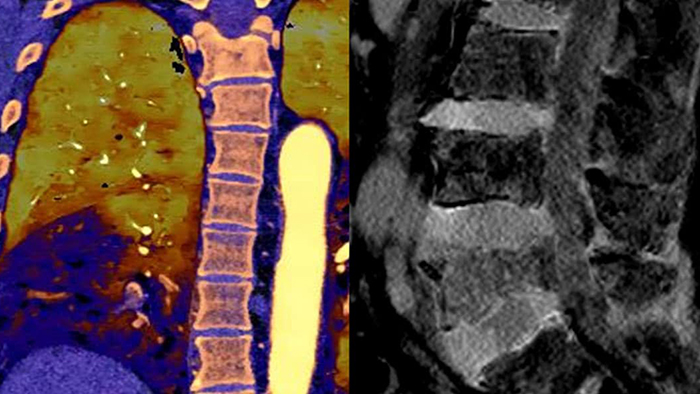

A differenza delle immagini TC tradizionali, le immagini della TC basata su detettore spettrale catturano le informazioni spettrali per il 100% del tempo, senza pianificazione o configurazione speciali. Ciò significa che è possibile analizzare in retrospettiva i dati spettrali di qualsiasi immagine, utilizzando diversi strumenti di visualizzazione spettrale. È possibile, ad esempio, regolare il livello monoenergetico oppure ottenere la mappa Zeffective.

Il detettore spettrale assorbe e differenzia simultaneamente l'energia alta e bassa da un singolo fascio di raggi X polienergetici. I risultati spettrali vengono acquisiti all'interno di una singola scansione senza la necessità di ricorrere a modalità speciali.

La TC spettrale mi aiuta a differenziare in modo obiettivo la colorazione con contrasto dall'emorragia, eliminando la necessità di ulteriori scansioni di follow-up e di un'osservazione prolungata del paziente, con conseguente riduzione dei costi e dell'esposizione alle radiazioni per i pazienti.1,2